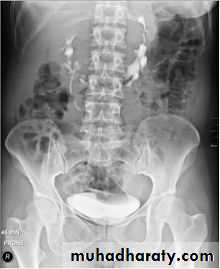

Horse shoe kidney -Kidneys may fail to separate.

-Almost invariably the lower poles remain fused.

-The kidneys axes are more parallel to the spine and malrotated.

-Diagnosis can be made by plain x-ray in some cases.

-US, CT scan and MRI can better demonstrate the anatomy and morphology hence the diagnosis.

-May be an incidental finding.

-PUJ obstruction and calculi formation are common .

IVU shows

1. The kidneys at low position .

2.Close to the spine with long axis parallel to the spine .

3. Malrotation manifested by medially directed calyces.

4- The renal pelvis and ureters are anterior and lateral in position .